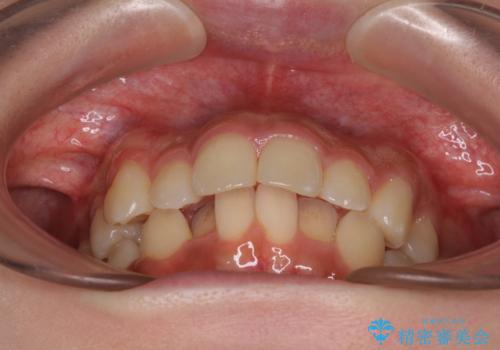

- 上顎前歯の突出感を気にして来院された患者様です。

上下左右第一小臼歯4本を抜歯して、積極的に口元を引っ込めるよう、ワイヤー装置にて矯正治療を行うこととしました。

抜歯矯正により、下唇が前方に突出した感覚が大幅に改善されました。